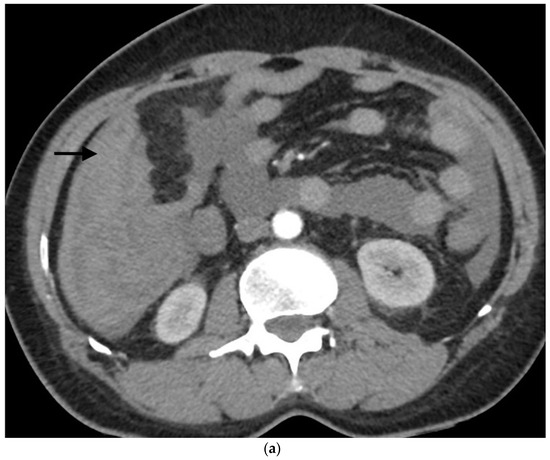

- Sandomenico, F.; Arpaia, V.; De Rosa, F.; Catalano, O.; Buonaiuto, R.A.; Notarangelo, M.; Iovino, M.; Giovine, S.; Brunetti, A.; Scaglione, M. Spontaneously ruptured hepatocellular carcinoma: Computed tomography-based assessment. Diagnostics 2023, 13, 1021. [Google Scholar] [CrossRef]

- Kim, H.C.; Yang, D.M.; Jin, W.; Park, S.J. The various manifestations of ruptured hepatocellular carcinoma: CT imaging findings. Abdom. Imaging 2008, 33, 633–642. [Google Scholar] [CrossRef] [PubMed]